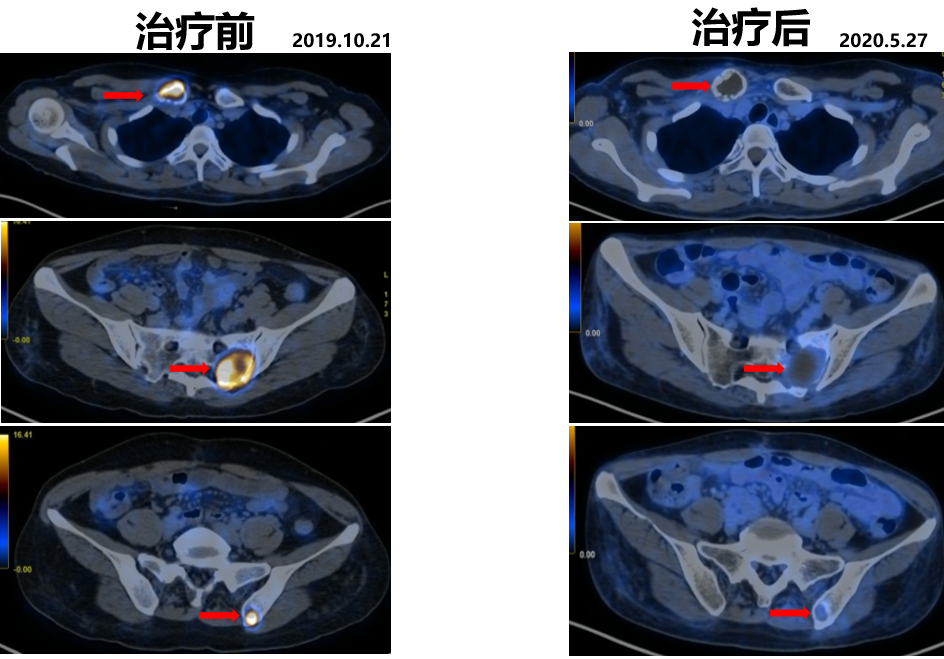

复查PET-CT:右侧锁骨、骶骨、及左侧髂骨局部骨质破坏并代谢活跃,考虑转移。

△PET-CT显示多处骨质破坏并代谢活跃

2019.10.21开始舒尼替尼50 mg po QD治疗(4/2方案)。

2020.05.27复查PET-CT病灶稳定,代谢较治疗前明显减低。影像学评估SD。

△舒尼替尼治疗后病灶稳定,代谢较治疗前明显减低